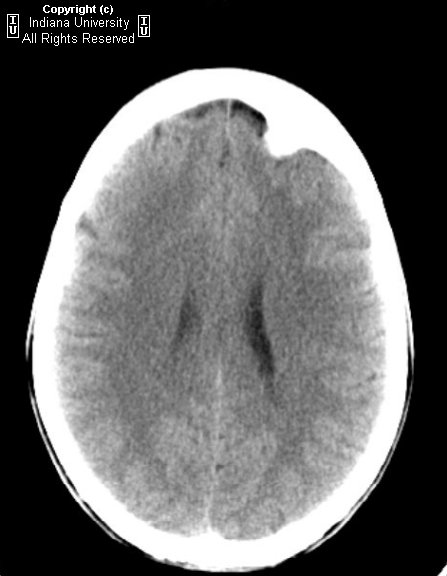

Что такое кортикальный гиперостоз: Симптомы и диагностика